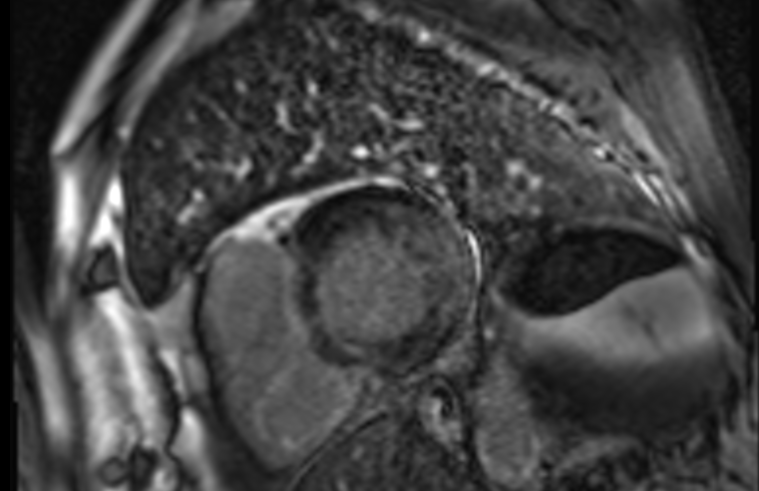

An ambulatory cardiac magnetic resonance was performed at discharge reporting moderate LV hypertrophy (15mm) with multifocal late gadolinium enhancement mostly midwall and predominantly located in the lateral basal segment. No T1 mapping or extracellular volume analysis was performed. The report suggested that this pattern might be suggestive of Fabry disease and consequently the patient requested a second opinion in another local hospital were serum alpha-galactosidase activity was reduced 0.40 nmol/h/ml (Reference range: 2.40-10.20).

Cardiac involvement is defined by left ventricular hypertrophy, short PR interval with increased voltages in the ECG. Basal inferolateral fibrosis and low native T1 mapping at cardiac magnetic resonance can be identified in early stages of the disease with progressive pseudonormalization of T1 in areas with fibrosis.